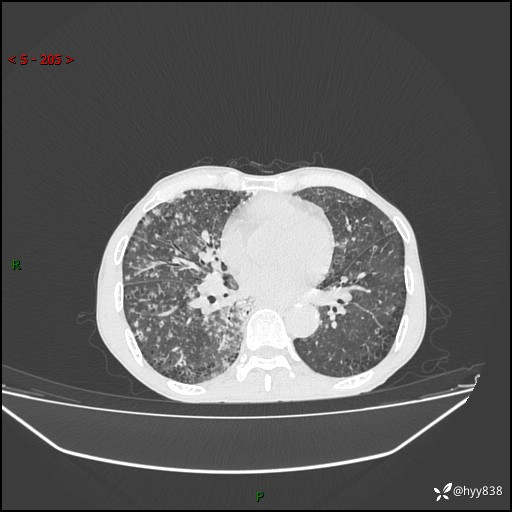

胸部CT平扫